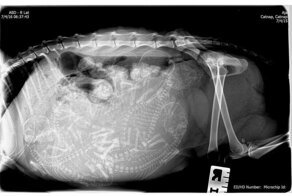

Так выглядят рентгеновские и ультразвуковые снимки беременных животных.

Беременная кошка